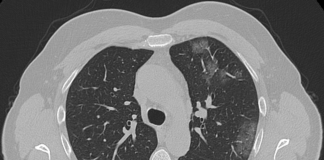

Controllo TC di uomo 57 anni privo di comorbilità e fattori di rischio rilevanti,ricoverato da oltre 30 gg in Terapia Intensiva attualmente in IOT con ventilazione meccanica alternata SIMV-CPAP e in terapia...